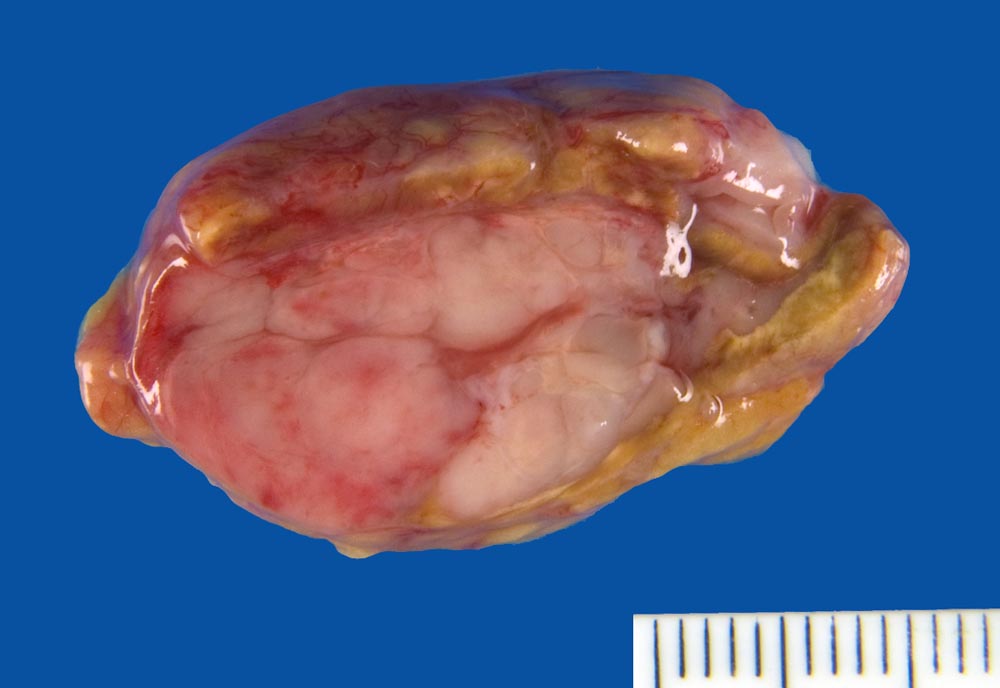

Infiltrate eines Plasmazellmyeloms in der Nebenniere

Knotige weisse Tumorinfiltrate in der Nebenniere.

Autoptisch: Infiltration des Knochenmarks mit osteolytischen Herden im 5. Lendenwirbelkörper, Rippen, Beckenkamm, Sternum. Infiltration der Lunge links mit Schwerpunkt im Unterlappen, Infiltration der Pleura visceralis und parietalis links und der Pleura visceralis rechts. Seröse Pleuraergüsse (links: 3.3 l, rechts: 0.9 l). Mediastinaler Tumor (Dm 10cm) mit Übergreifen auf die Brustwand. Perikardinfiltraton. Infiltrate in Leber (Dm bis zu 3.5cm), Milz, Haut (Dm bis zu 0.8cm), Peritoneum, Nebenniere links, peripankreatische Lymphknoten, perirenales Weichteilgewebe.

Multiples Myelom IgG Kappa, Erstdiagnose vor 2 Jahren. Zustand nach 6 Zyklen Chemotherapie über 6 Monate und Radiotherapie vor 2 Jahren. Zustand nach 11 Zyklen Chemotherapie über 9 Monate und Radiotherapie über 2 Wochen bei mediastinalen und zervikalen Lymphknotenmetastasen seit 11 Monaten. Zustand nach rezividierenden malignen Pleuraergüssen seit 2 Monaten und Pleurapunktionen.